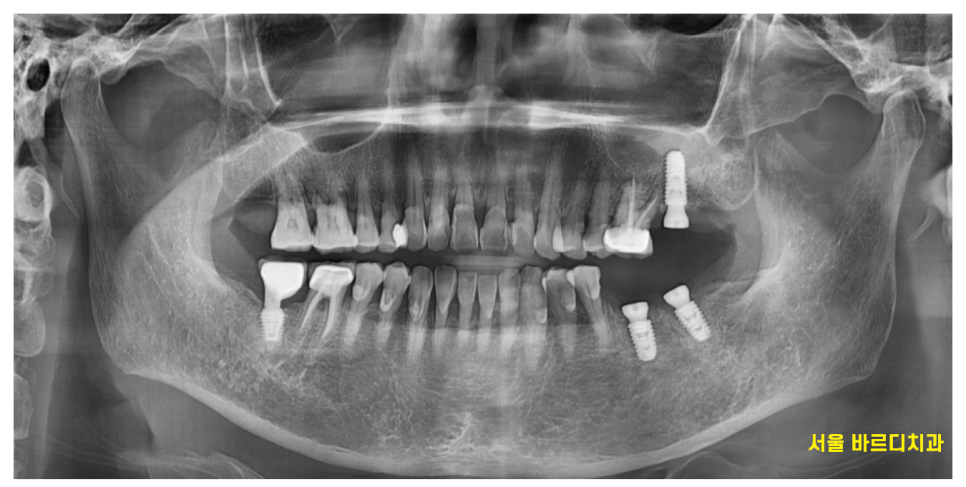

이가 흔들려 내원한 환자분입니다.

23.10.04

역시나 잇몸뼈가 많이 내려간 것을 확인하였습니다.

23.09.26

그중에서도 왼쪽 맨 끝에 치아가 심각했습니다.

뿌리를 감싸고 있는 뼈가

까맣게 보이네요~

염증으로 많이 녹기도 하였고

어금니 흔들림을 동반한 통증

느끼실만큼 많이 상하였습니다.